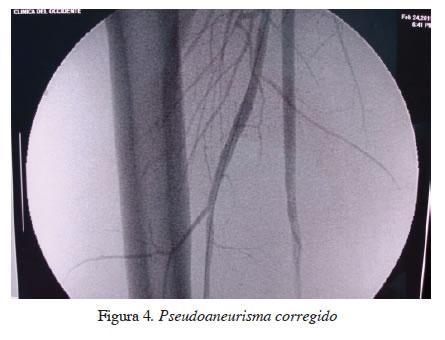

Durante un periodo de dos años se trataron por vía endovascular siete pacientes con trauma vascular periférico, así: uno con seudoaneurisma y fístula carotídea yugular; dos con fístulas arterio-venosas en la región femoro-poplítea; una paciente con laceración de la segunda porción de la arteria subclavia izquierda por herida por arma de fuego con presencia de shock; uno con un seudoaneurisma roto del tercio proximal de la arteria tibial anterior (figuras 1 y 2); uno con trauma pélvico cerrado con sangrado secundario a lesión de la arteria ilio-lumbar izquierda, y un paciente con un seudoaneurisma de la arteria femoral profunda secundario a una herida por arma corto-punzante (figuras 3 y 4). Los pacientes se numeraron del 1 al 7.

Desde enero de 2010 hasta enero de 2012 se hizo tratamiento endovascular en siete pacientes, dos (28 %) mujeres y cinco (72 %) hombres. La edad promedio fue de 34 años (rango, 18 a 54). En la distribución por mecanismo de trauma se encontró que un paciente (14 %) tuvo trauma pélvico secundario a accidente de tránsito (laceración de la arteria ilio-femoral) y seis (86 %) tuvieron trauma penetrante, cuatro (66 %) de ellos por arma de fuego y dos (34 %) por arma corto-punzante. Un (14 %) paciente tuvo lesión en la arteria carótida izquierda y otro en la arteria subclavia izquierda. Cinco (72 %) tuvieron lesiones en miembros inferiores, uno (20 %) en la arteria femoral profunda derecha, dos (40 %) en la arteria poplítea, uno (20 %) en la arteria tibial anterior y uno (20 %) en la arteria ilio-lumbar. En la distribución por diagnóstico se encontró que tres (43 %) pacientes tuvieron fístula arterio-venosa, tres (43 %) presentaron seudoaneurismas y uno (14 %), una laceración arterial completa. El método anestésico utilizado para la reparación fue anestesia local en seis (86 %) y anestesia general en uno (14 %) (lesión de la arteria subclavia). En seis (86 %) de los siete pacientes fue posible la implantación de un estent y en uno fue necesaria la formación de un émbolo (arteria ilio-lumbar) utilizando espirales de acero (coils). El tiempo promedio de duración del procedimiento quirúrgico fue de 60,7 minutos (rango, 40 a 90). En todos los pacientes se comprobó éxito angiográfico y permeabilidad del vaso lesionado.